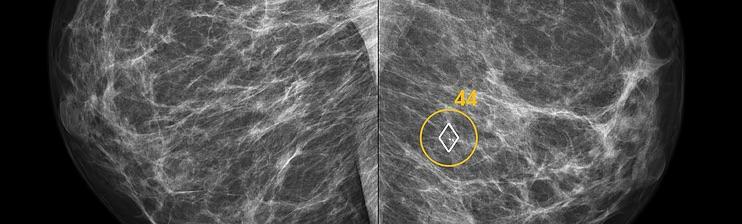

ScreenPoint recently announced it has received 510(k) clearance from the U.S. Food and Drug Administration (FDA) for Transpara detection and decision support software, designed to assist radiologists with the reading of screening mammograms. Transpara is the first AI application for detecting breast cancer in screening mammograms to gain FDA 510(k) clearance, based on its functionality that interactively provides support for detection and diagnosis.

“Compared to traditional mammography computer-aided detection (CAD) products, ScreenPoint’s decision support product Transpara delivers much more clinically useful information to the radiologist,” said Ritse Mann, M.D., Ph.D., breast imaging specialist at Radboud University Medical Center, Nijmegen, Netherlands, who uses the system clinically and evaluated its performance in several studies, “I can use Transpara as a second reader and its opinion is as good as when I would ask a colleague.”